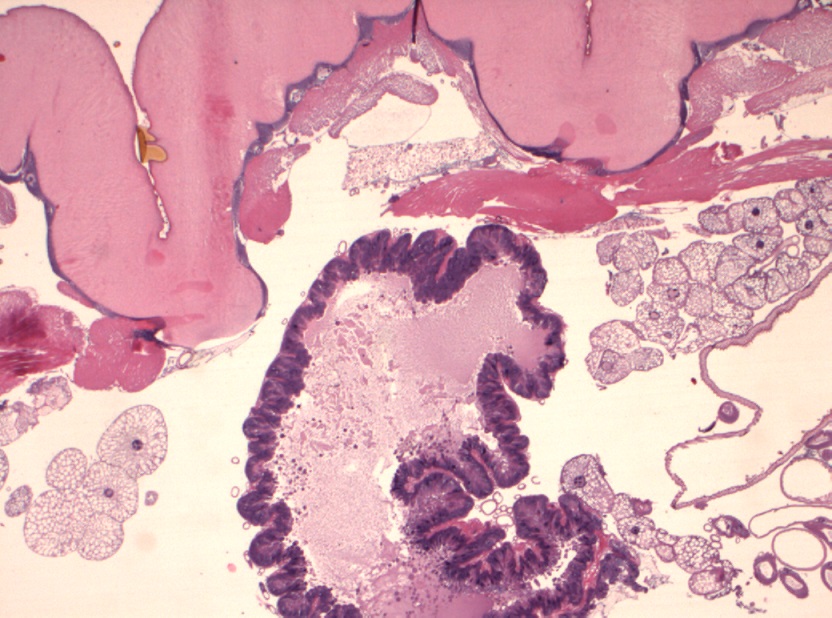

Foto microscopiche: purtroppo non ho potuto fare foto "panoramica"; ho fatto alcune foto al minore ingrandimento; si possono osservare le componenti della larva caratterizzata da spessa cuticola con sparse "spine" in superficie, che penso che siano i rostri; internamente alla cuticola si osserva strato di tessuto muscolare liscio ed organi interni conservati; ho fatto anche una foto del lembo di cute e sottocute sovrastante centrato da tragitto fistoloso circondato da denso infiltrato infiammatorio costituito da linfociti, plasmacellule, istiociti e più rari granulociti eosinofili.

Io vi metto due foto macroscopiche e quelle istologiche, che in pratica rappresentano le "fette" della larva partendo da un'estremità (bocca?), poi il centro (forse l'apparato digerente?) e l'altra estremità...spero siano sufficienti :)